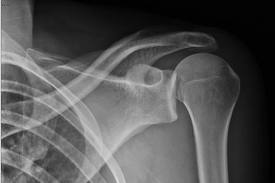

Guillaume Cuffel est victime d'une luxation de l'épaule, avec arrachement des ligaments (blessure identique à celle de Côme Lecossais il y a 15 jours).

Il a une luxation acromio-claviculaire complète... Pour résumer, les ligaments qui retiennent la clavicule à l'omoplate ont "sauté"!!!

Il s'est fait poser 2 broches... Entre la rémission, et la ré-éducation, il ne va pas pouvoir jouer avant... ... longtemps